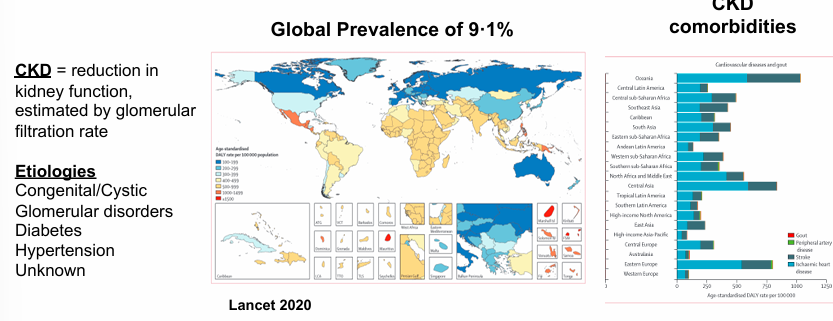

___ is a common cause of hypertension

-chronic kidney disease